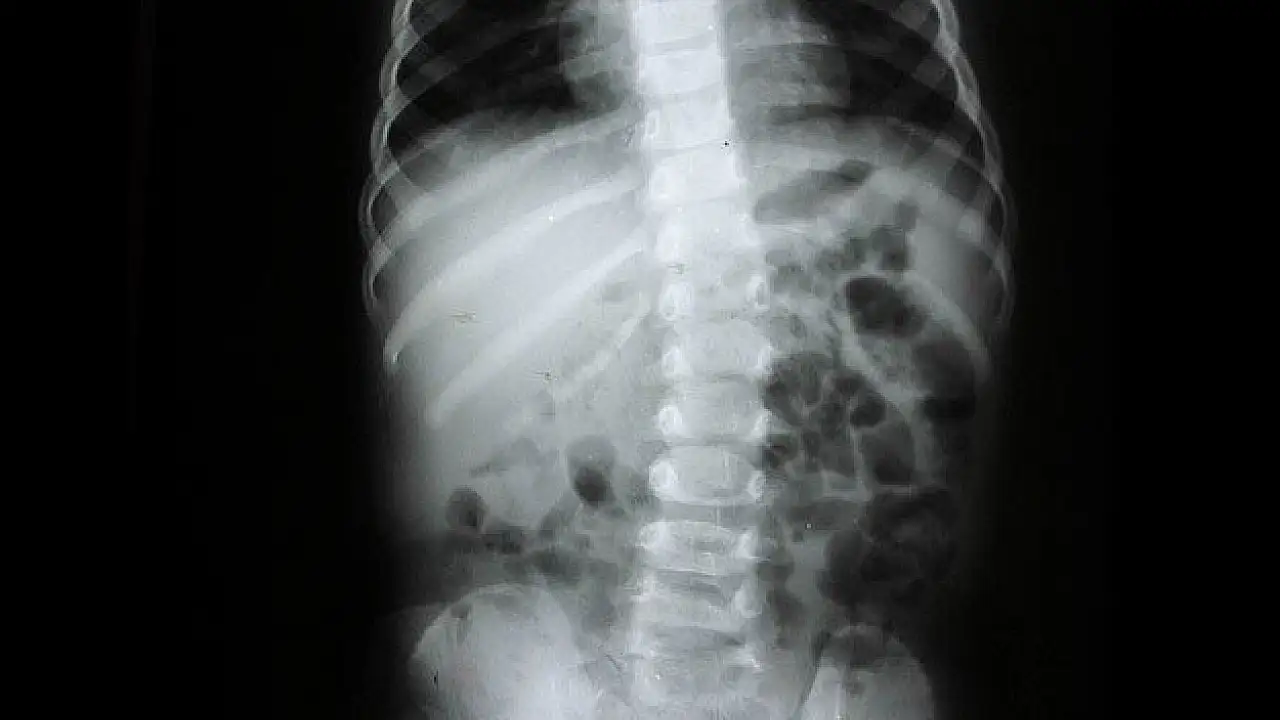

Eğriliğin erken dönemde fark edilmesi durumunda fizik tedavi, korse gibi yöntemlerle düzeltilebileceğini anlatan Yücesoy, yüzde 20 eğrilik döneminde bükülmeyi izlediklerini, yüzde 20 ve 45 eğrilik düzeyinde fizik tedavi, egzersiz ve korse uygulamaları önerdiklerini, eğim arttıkça ameliyatı tercih ettiklerini ifade etti.

Skolyozun toplumda rastlanma sıklığının yüzde 1-2 arasında değiştiğine işaret eden Kemal Yücesoy, "Skolyozda sadece o kemiğin çıkarılması ve altının ve üstünün birbirine bağlanması sonra meydana gelebilecek daha büyük rahatsızlıkları önlüyor.40-45 derece gibi ileri boyutta eğrilik olduğunda ise bunu rijit sistemlerle, vidalarla ve ona bağlı çubuklarla düzeltiyoruz" diye konuştu.